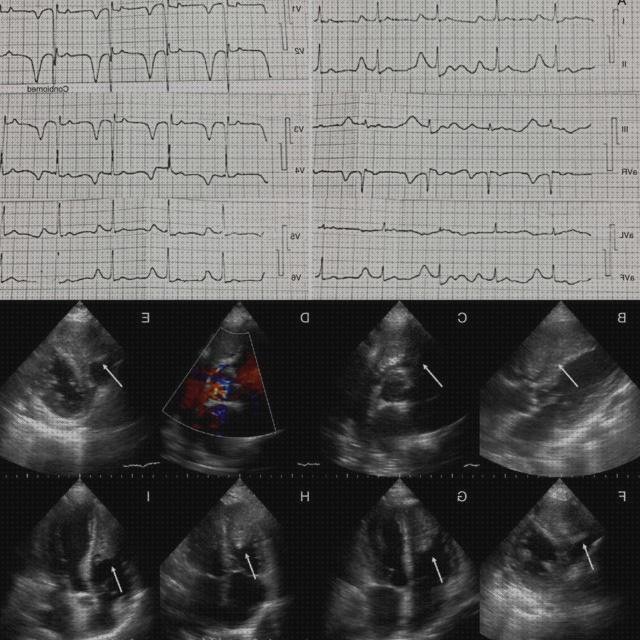

Hoy día muchas federaciones deportivas la requieren a sus atletas debido a que aporta datos de relevancia en cuanto a casual dolencias cardíacas. El electrocardiograma recoge la actividad eléctrica del corazón, esto es, el impulso que provoca que este mismo se contraiga y bombee la sangre de manera eficaz. Mediante unos electrodos puestos en sitios estratégicos se determinan los impulsos del corazón desde distintos ángulos.

El ecocardiograma nos deja “ver” el estado natural de nuestro corazón, si existe alguna anormalidad a ras de forma, volumen, potencia (puesto que corazón es un músculo), el funcionamiento de las válvulas, las presiones que aguanta e tambien el grosor de las paredes del mismo.

Un cardiólogo puede observar el funcionamiento de nuestro “motor” y descubrir entre otras cosas, si existiese un derrame, un tamaño anómalo de algún hueco, o una fuga en el cierre de una válvula (comúnmente famosa como inspiración).

¿qué instrucciones nos da el electrocardiograma?

El electrocardiograma presenta unos trazos individuales en el caso de cada deportista, las variaciones que tiene la posibilidad de entrar a mostrar indican al médico si se encuentra frente a un problema cardíaco. Entre los parámetros que el electrocardiograma revela durante la prueba encontramos el ritmo y la regularidad, pudiendo descubrir trastornos actuales e tambien previos en el día de la prueba.

Entre las patologías que deja encontrar encontramos bloqueos de aurículas, arritmias o tambien infartos previos no diagnosticados, por lo que su ejecución antes de cualquier prueba deportiva es una enorme medida de prevencion.